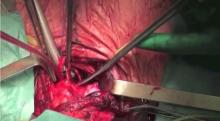

A cervicotomy was performed. The pretracheal planes were sharply and bluntly dissected from adhesions caused by previous radiotherapy. Laryngotracheal release was performed to maximize tracheal mobilization. On the basis of tracheal measurements acquired during pre-operative rigid bronchoscopy, the trachea was proximally transected and separated from the esophagus. The orotracheal tube was then retracted, the tracheal lumen opened, and the involved tract resected. Cross field ventilation was started, followed by proximal ring resection. Laryngeal release was optimized. Airway reconstruction was accomplished by 2/0 PDS running suture of the pars membranacea and 2/0 PDS single stitches on the cartilaginous rings. The endotracheal tube across the field was removed and the orotracheal tube was drawn into the field and positioned beyond the anastomosis. Two more crico-tracheal stitches were placed to reduce tension on the anastomosis.